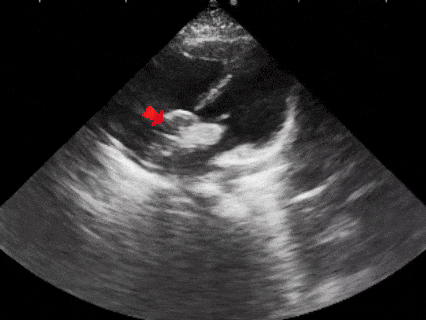

术前复测

多切面测量房间隔缺损直径为

20.5mm×22.0mm×21.6mm

多普勒下可见房水平左向右分流